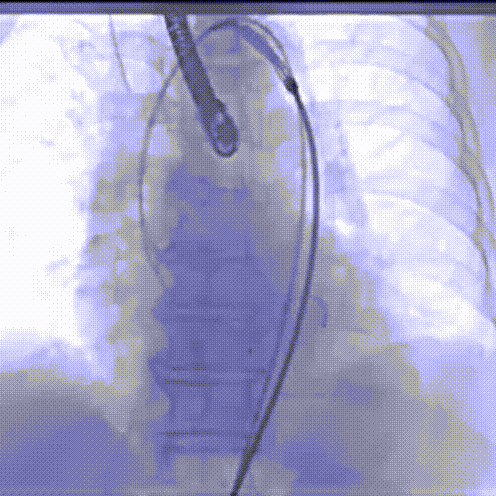

TaurusOne轻松过弓

瓣膜定位

瓣膜释放